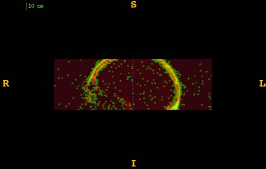

Figure 1 shows the examples of pixel selection masks generated using tested approaches at the highest resolution level for pixel sampling rate 0.5%. It is obvious that the samples generated with the URS approach are extremely spread, whereas the samples generated with the GMS approach are overly concentrated along the gradient magnitude structures present in the image. The proposed approach produces samples that balance those two extremities.